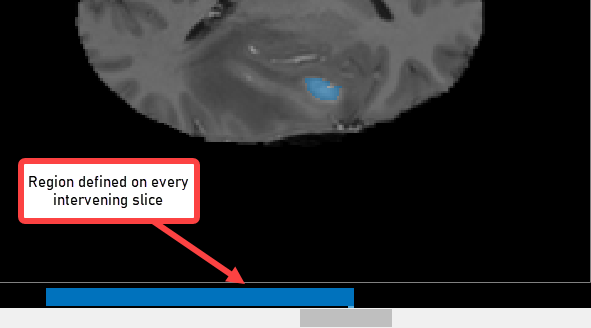

To use interpolation, you must first manually define the region on two slices. You have already defined the region on the first slice where the object appears, slice 35. Use the same process to define the region on the last slice where it appears, slice 88. The app places two bars on the slider, using the color associated with the label, to indicate the slices with ROIs.

With the ROI defined on two slices, click Auto Interpolate. The app automatically defines the ROI on all the intervening slides. The app uses blue bars to indicate all the slices that have ROIs, which now appear like a solid bar from slice 35 to slice 88.